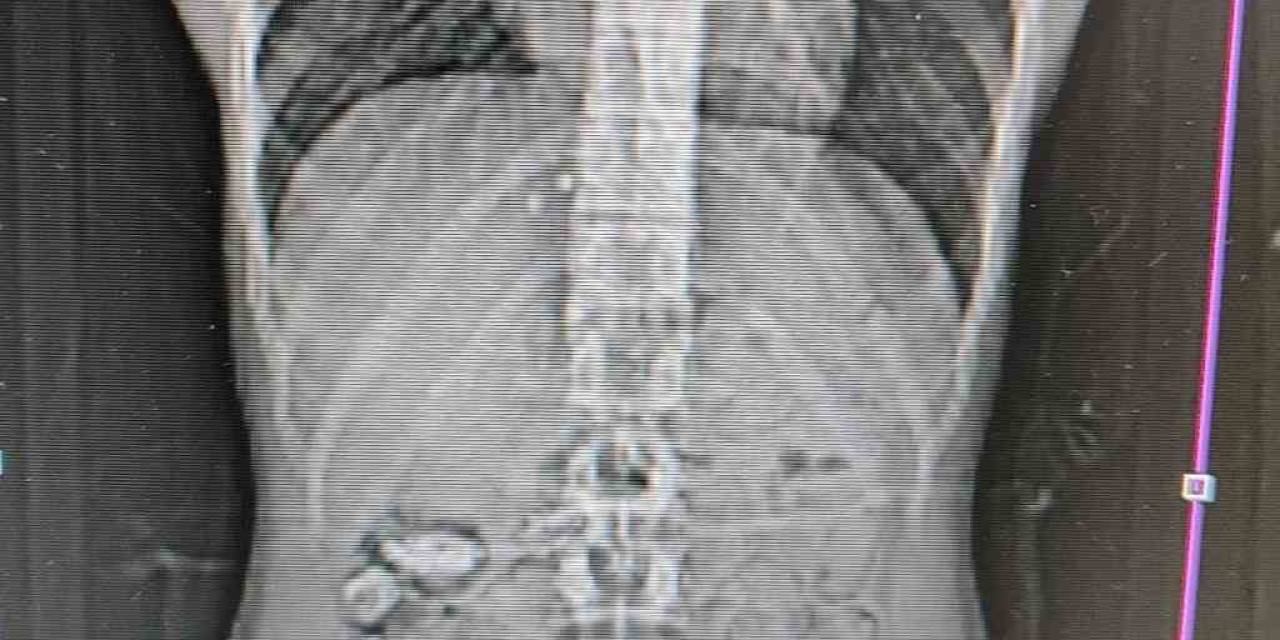

Uyuşturucu Kuryesinin Midesinden 18 Kapsül Çıktı